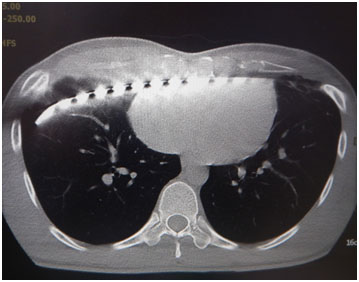

一年多前, 曾來我門診, 經檢查有明顯廣泛型凹胸併有心肺壓迫, 胸骨至脊椎間距只有6.9公分, 最近又來門診, 已經在他院做過手術, 但仍明顯呼吸矯促, 再做檢Dr. 朱志純 發表在 痞客邦 留言(0) 人氣(770)